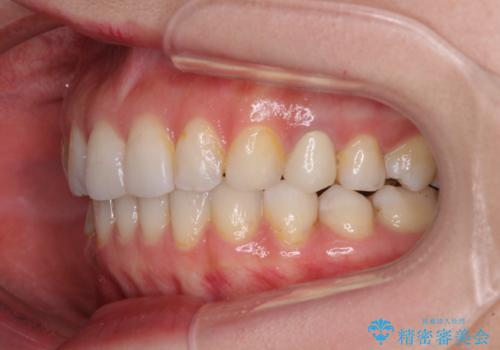

長時間のマウスピース装着と、患者様自身でのゴムかけに協力いただき、自然な口元に仕上げることができました。

気になっていた変色した歯もオールセラミッククラウンで本物の歯のようになり、患者様には大変満足していただきました。